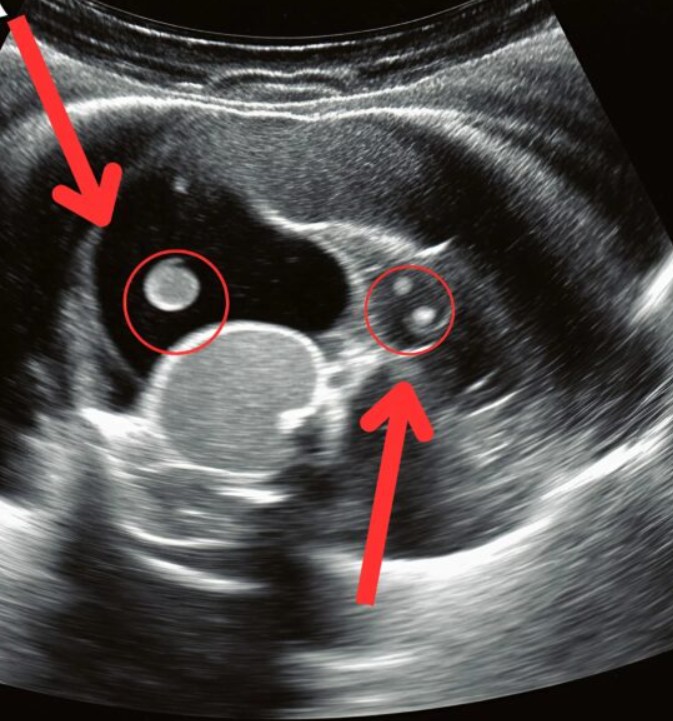

Chodby pohotovosti se zdály zmrzlé v čase. Sledujíc dceru, jak se kroutí na nosítkách v bolesti, čekaly jsme na výsledky ultrazvuku pod obavnými pohledy lékařů. Nakonec k nám přišel doktor a pronesl větu, kterou žádný rodič nechce slyšet: „Je nutná okamžitá operace.“ Ukázalo se, že ty bolesti zad, které jsme připisovali batohu, byly ve skutečnosti způsobeny tiše rostoucím ledvinovým kamenem. Kámen se posunul do močovodu, což způsobilo nesnesitelné bolesti a ohrožení života.